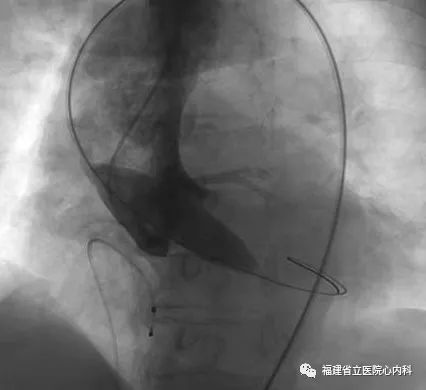

该病例是一个单纯重度主动脉瓣返流患者,主动脉瓣上没有稳定的锚定结构,通过依靠瓣环及左室流出道,瓣膜移位及瓣周漏风险大,手术难度极大,术者通过CT仔细制定了手术策略及各种预案,最终顺利植入29号瓣膜,术后无返流及瓣周漏,手术效果佳。

植入L29瓣膜